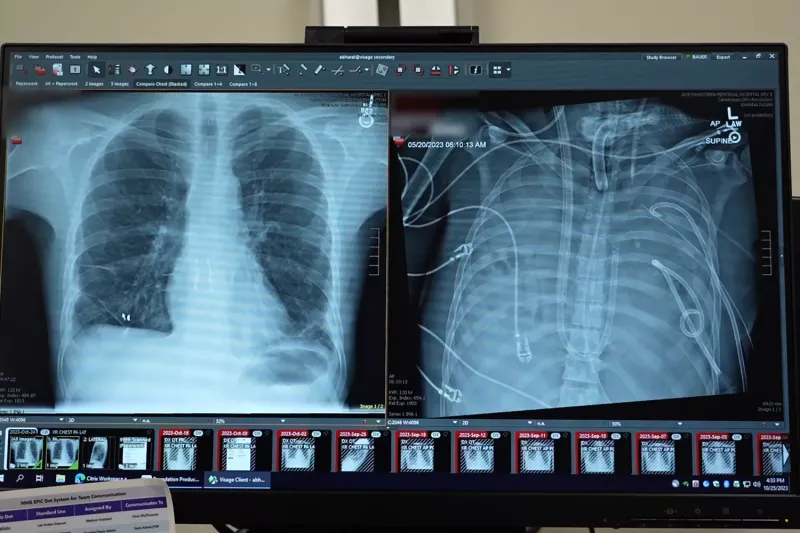

Photo of old and new lungs